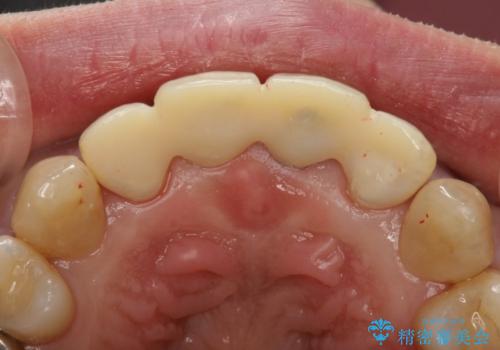

左上の1番目の前歯が審美的に気になるとのことで、前歯の審美修復を行う事になりました。患者さまのご希望により、前歯4本を一緒に修復することでより審美的な結果を得ることができたと思います。

仮歯も綺麗に仕上げることで、歯ぐきの状態が良くなり、綺麗な型がとれます。ひいては最終的な被せものの仕上がりもよくなるわけです。このような治療は、毎回の妥協なき診療が結果に結びつくといえます。

なお、仮歯が連結されているのは矯正治療直後であったため後戻りを防止するためです。本来はフロスが通るよう個別にしてあげた方が良いですね。最終的な被せものは個別の設計で、改めて後戻り防止用のマウスピースを製作しています。

被せものの種類:e.max プレスクラウン (エコノミー)